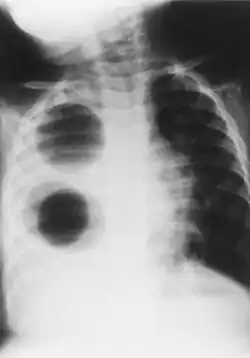

- Chest X-ray is effective in detecting the traits of lung herniation.[1] The unaffected side of lung tends to undergo hypertrophy, and move towards the empty space in the chest wall on the opposite side.[1] This herniation could be indicated by fluoroscopy.[1] With age increasing, the herniation progresses and ease its detection.[1]